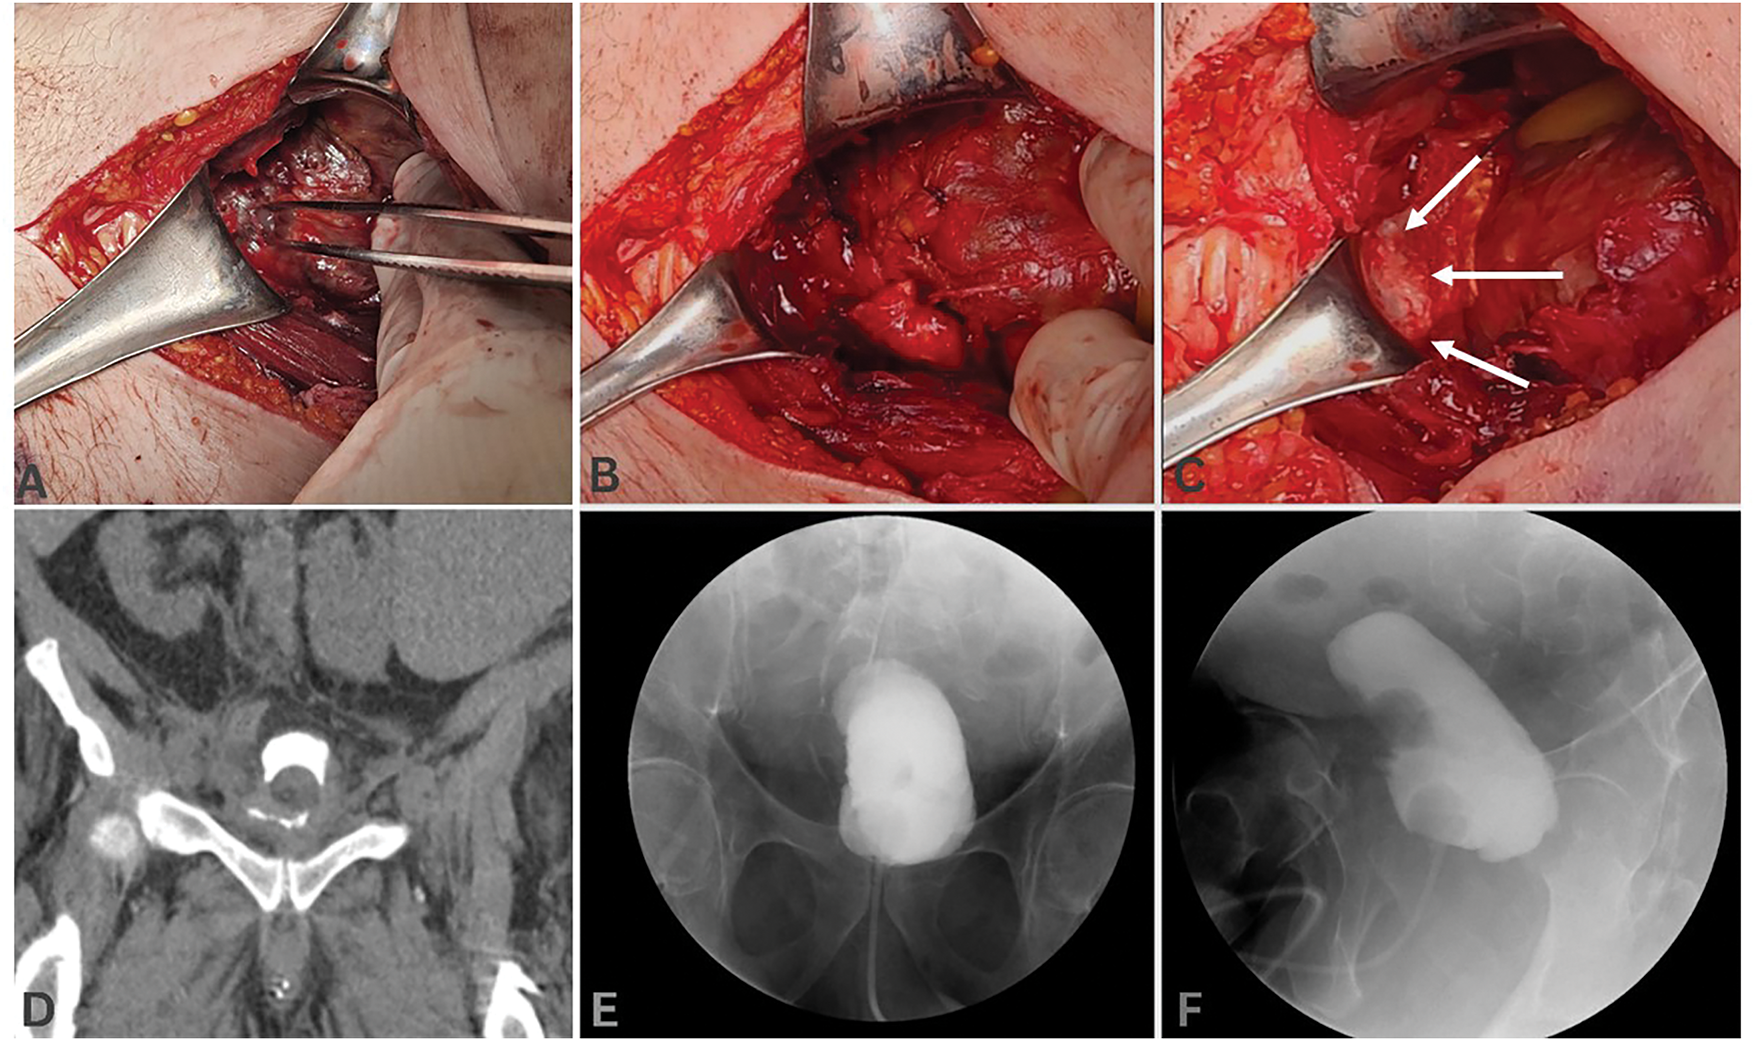

Through a low midline abdominal incision, the space of Retzius was developed. After evacuation of the old pelvic hematoma and urinoma, a 2 × 2 cm bladder defect on the anterior bladder wall was identified (Figure 3A), along with severe inflammation and severe ischemia around the site of perforation. The bladder repair was performed using 0-PDS running stitches in two layers (Figure 3B). To enhance tissue sealing, a 3 × 3 cm absorbable fibrin sealant patch (TachoSil®, Baxter, CA, USA) was applied and fixed at the site of cystorrhaphy for further reinforcement (Figure 3C). We avoided entry into the peritoneal cavity to allow further containment of any further urine leakage or recurrent hemorrhage. The bladder was drained with a Foley catheter A cystostomy tube and an external drain were placed in the pelvic cavity.

FIGURE 3. Intraoperative view of the bladder after development and exploration of the Retzius space through a low midline abdominal incision. After identification of (A) the site of bladder rupture, it was repaired in (B) two layers and was reinforced by placement of (C, arrows) a 3 × 3 cm absorbable fibrin sealant patch (TachoSil®, Baxter, CA, USA). (D) Post-operative CT-cystogram 6 weeks after the surgery showed minimal persistent urine extravasation. No urine leakage was demonstrated 8 weeks after the surgery on X-ray cystogram, (E) coronal, (F) sagittal views

Total operative time was about 140 min, and the patient tolerated the procedure well, with no ongoing blood loss from the pelvic cavity. The patient was discharged on postoperative day 6 with a Foley and cystostomy tube. A postoperative cystogram, 6 weeks after the surgery, showed improvement, but persistent urine extravasation (Figure 3D). At 8 weeks after the surgery, the integrity of the bladder was confirmed with a repeat cystogram (Figure 3E,F). Subsequently, the Foley was removed, and after clamping of the cystostomy, the patient had a spontaneous voiding pattern. Following one week of clamping, the cystostomy was finally removed. The patient was subsequently lost to follow-up, and no data on his voiding symptoms or characteristics could be obtained.

As shown on serial postoperative cystograms (Figure 3D–F), the course of bladder repair in the setting of ischemia might be prolonged compared to traumatic bladder rupture. This allows maximal opportunity for healing and reduces the risk of recurrent perforation in the postoperative period. Consideration should also be made for resulting bladder dysfunction or detrusor hypocontractility after ischemic injury, which can be evaluated using uroflowmetry and post-void residual measurements. Due to the limited number of cases of SRUB and the fact that many of these patients are clinically unstable, studies designed to compare the outcomes of early surgical intervention versus conservative management, although advisable, are difficult to undertake.